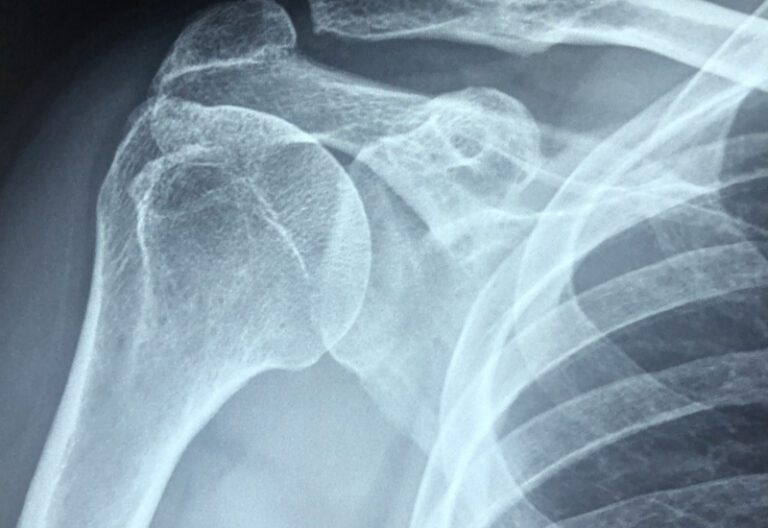

Apa Itu Penyakit Frozen Shoulder . Sendi bahu merupakan sendi paling fleksibel dan memiliki rentang gerak paling luas. Frozen shoulder atau adhesive capsulitis merupakan suatu kondisi peradangan yang ditandai dengan kekakuan dan nyeri pada bahu. Ini gejala, penyebab, dan pengobatannya. Frozen shoulder atau adhesive capsulitis merupakan suatu kondisi peradangan yang ditandai dengan kekakuan dan nyeri pada bahu. Frozen shoulder atau kapsulitis adesif adalah kondisi yang ditandai dengan kekakuan dan nyeri pada sendi bahu. Pada frozen shoulder biasanya terjadi proses. Frozen shoulder adalah gangguan yang disebabkan oleh adanya penebalan pada kapsul pelindung bahu. Frozen shoulder atau disebut juga dengan adhesive capsulitis adalah peradangan pada sendi bahu sehingga menyebabkan nyeri dan kekakuan. Bahu beku atau frozen shoulder adalah suatu kondisi yang membuat rentang gerak bahu jadi terbatas.